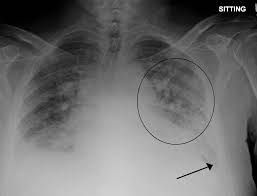

Treatment of acute pulmonary edema can easily be remembered by a mnemonic "LMNOP" L - loop diuretics M - morphine N - nitrates O - Oxygen P - position (sit the patient up)

Yes we sit the patients up and order diuretics. preform a echo and ecg w/ Troponin to r/o cardiac events. Order a Renal panel to r/o kidney failure CT thorax with and without contrast for better evaluation. If plural effusion present = thorethenesis Alot of pulmonary edema pt are cardiac or renal so this amount of plural effusion patients are small.